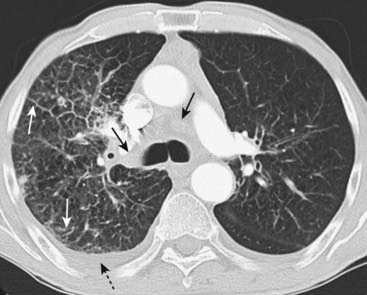

Figure 12-21 Saddle and peripheral pulmonary emboli.

Acute pulmonary emboli appear as partial or complete filling defects centrally located within the contrast-enhanced lumina of the pulmonary arteries. A, A large pulmonary embolus almost completely fills both the left and right pulmonary arteries (solid white and black arrows). This is a saddle embolus. B, A small, central filling defect is seen in a more peripheral pulmonary artery (dotted white arrow). This pulmonary artery seems to be floating disconnected in the lung because the plane of this particular image does not display its connection to the left pulmonary artery.